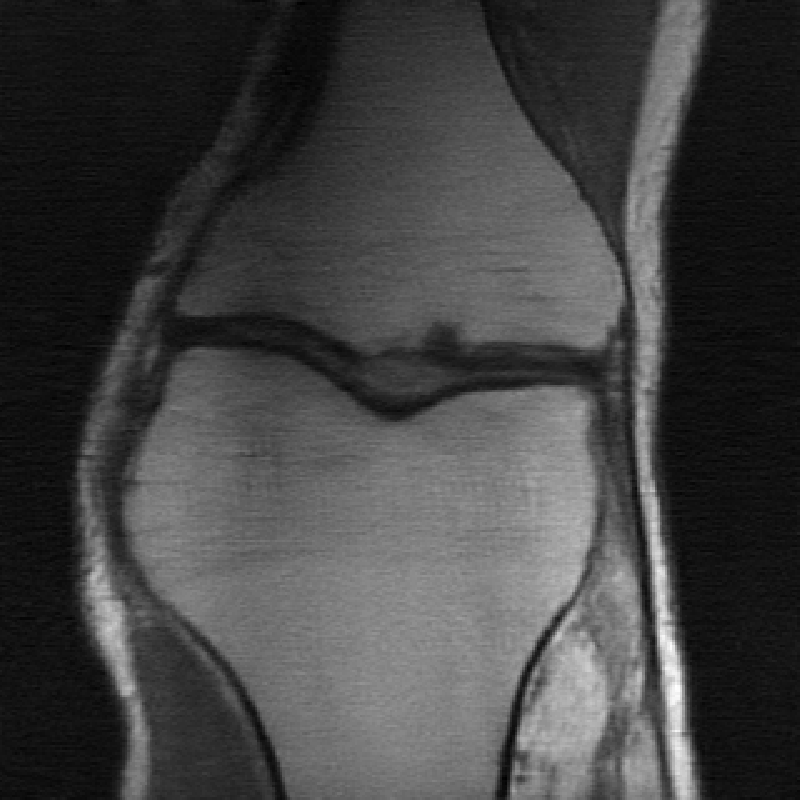

The data used in the undersampled MRI experiments were obtained from the NYU fastMRI Initiative [45]. The primary goal of the fastMRI dataset is to test whether machine learning can aid in the reconstruction of medical images. We trained and tested on a subset of the single-coil knee dataset, which consist of simulated single-coil measurements. In all tests, we use complex-valued data, which interfaces with our deep networks by treating the real and imaginary parts of the images as separate channels. We measure reconstruction accuracy with respect to the center 320320 pixels of the complex IFFT of the fully-sampled k-space data. For the purpose of visualization, we display only the magnitude images in the following sections.

In Table 1 we present our main results. We present sample reconstructions for the deblurring problem and MRI reconstruction problem in Figs. 7 and 8. For reference, the ground truth, inputs to the networks, a total variation regularized reconstruction, and a RED reconstruction are presented in Figs. 5 and 6. We also provide in the Appendix a table of SSIM values as well as the full version of Table 1, which contains the standard deviations of PSNR.

While the magnitude of the improvements vary across domains and problems, we find that retraining the network with the proposed model adaptation techniques significantly improve performance by several dBs in the new setting. This effect is particularly striking in the case of MRI reconstruction with MoDL, where the βnaiveβ approach of replacing with in the network gives catastrophic results (a roughly 9 dB drop in reconstruction PSNR), while the proposed model adaptation approaches give reconstruction PSNRs within 1-2 dB of the baseline approach of training and testing with the same forward model in the case where is known.